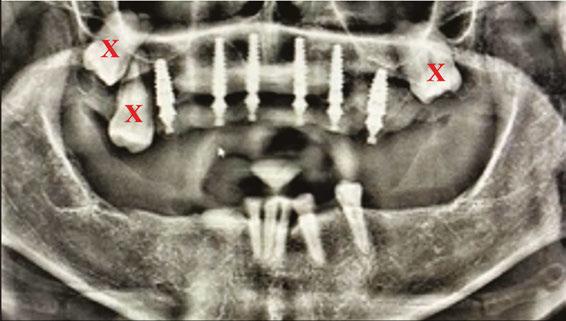

Mr. Z has a skeletal Class III malocclusion. He has never received orthodontic treatment. The CBCT shows tooth No. 6 is present but horizontally impacted (Figure 4).

Based on age of patient, health history, and presence of the impacted canine, the patient was sent to an oral surgeon for evaluation. The initial consultation asked the surgeon to consider removal of impacted tooth No. 6 and placement of bone graft as a prelude to restoring site 2-7 with an implant-supported fixed bridge (Figures

Close inspection of the CBCT shows tooth No. 6 is ankylosed. The oral surgeon indicated extraction of tooth No. 6 would require block resection of bone with the tooth. The resulting defect would have required extensive bone grafting

added time and cost to this case.

5 and 6). and Douglas D. Wright, DDS, is a general dentist in private practice in Staunton, Virginia. William T. Goodwin II, DDS, is a maxillofacial surgeon in private practice in Harrisonburg, Virginia. For questions about this article, please contact Dr. Wright at dominosign14@ gmail.com. Figure 1: Pretreatment photo of patient. Note the extreme wear of mandibular incisors occurring from uncorrected malocclusion. Also note the contact between tooth Nos. 9 and 22 when the mandible moves to the right. This “canine guidance” was incorporated into the fixed-bridge design on the patient’s upper right side Figures 2 and 3: Metal framework at try-in appointment. Porcelain-fused-tometal was used to restore this case because of lack of interarch space

On the day of surgery, the patient had MegaGen AnyRidge® implants placed at the following sites under local anesthesia:

• Tooth No. 7: trans-canine placement of 4.0 mm x 13 mm

• Tooth No. 3: 5.0 mm x 7.0 mm with small crestal approach sinus graft

• Tooth No. 13: 4.0 mm x 10.0 mm implant

Figures 7 and 8: Healing abutments in place Figure 4: Pretreatment panoramic x-ray. Note position of maxillary right canine Figures 5 and 6: Pretreatment CBCT scan with treatment planning software. Virtual implant placement at site 10 shows thin buccal bone. Buccal bone graft was provided at time of surgery Figures 9 and 10: Porcelain-on-metal framework ready for delivery

2. Paton G, Fuss J, Goss AN. The transmandibular implant: a 5- and 15-year single-center study. J Oral Maxillofac Figure 14. Post implant placement. This CBCT shows implant at site 10 through the impacted canine. Implant at site 3 was placed right against the sinus floor Figures 13A and 13B: 13A. Trans-mandibular dental implants. 13B. Subperiosteal implants Figure 11: Surgical site on day of surgery Figure 12: Implant placement of tooth No. 7 with buccal bone graft